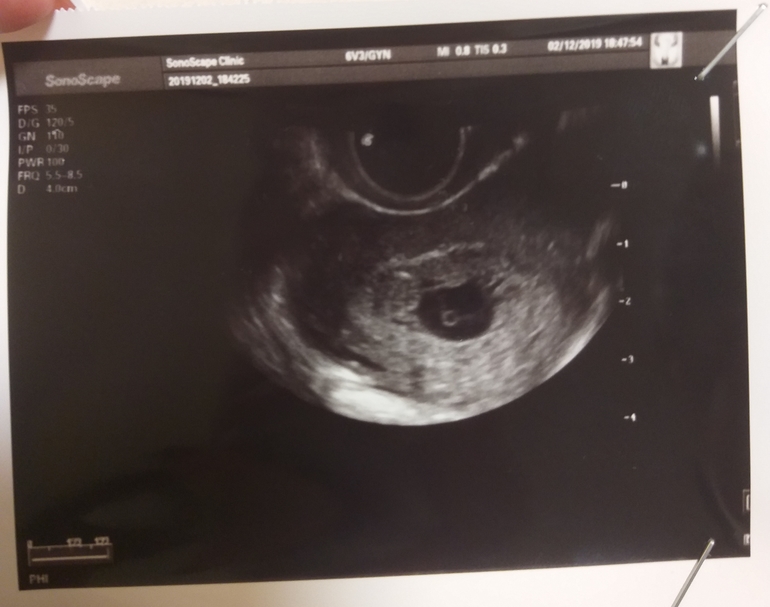

, никак не могу уснуть. 10 недель назад узнала о долгожданной беременности после планирования в 1,5 года. Сегодня в обед начались небольшие коричневые выделения , побежала на УЗИ,моего врача сегодня не было , была другая г и она меня просто так ошарашила словами ,что "10 недель тут точно нет , эмбриона нет, плодное деформировано, сердцебиения тоже нет,есть только желточный мешок 2 мм, который соответствует 5 неделям,он замер на 5 неделе" Я была на УЗИ крайний раз 2 недели назад,моя врач с другим врачом смотрели меня и ставили срок 5-6 недель эмбриональных,якобы была поздняя овуляция,был и эмбрион ,и сб+ , ладно бы один врач ошиблась,но там был ещё и врач мужчина ,и я видела своими глазами и слышала сб, как так ? Я целых 5 недель ходила с мёртвым малышом. Такое паршиво чувство.Сейчас там пустота. Прилагаю фото УЗИ. Муж запретил делать выскабливание. Сказал только медикаментозный. Сегодня выпила первую таблетку в 9 вечера . уже болит низ живота. Морально чувствую себя ужасно, и никак в голове не укладывается, как такое может быть, что был эмбрион и тут его уже нет. Исчез он куда то , убежал? Спрашивала у врачей , ничего толком ответить не могут : " такое бывает " и все. Может пояснит кто-нибудь....

На снимке у Вас действительно видно только желточный мешочек и эмбриона нет.